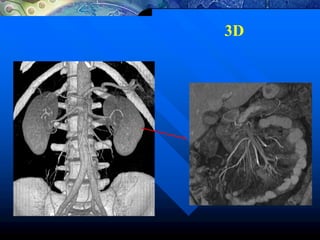

3D

120kV/230mA/2.5mmEsp/0.8seg

Volume Rendering MPVR/MIP

3D/Angio

Volume Rendering

Crânio Abdome

Volume Rendering MPR

Trauma

Facial

Reformatações Volumétricas

Pulmão

MPR 3D

Análises de vasos

Aorta